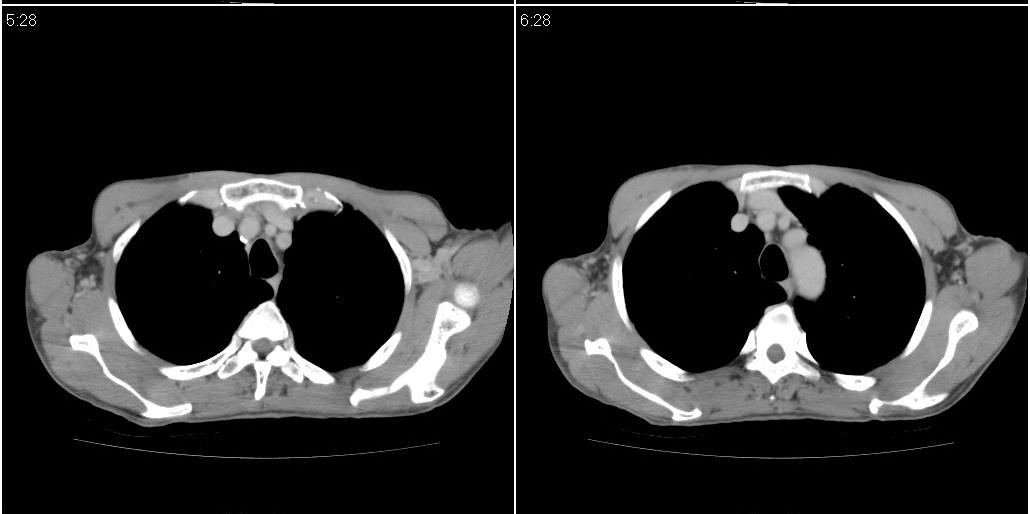

标题: CT25416:男性,70岁。胸片发现右下肺斑片状阴影 [打印本页]

标题: CT25416:男性,70岁。胸片发现右下肺斑片状阴影

以下是ct检查的情况:

标题: ct增强: